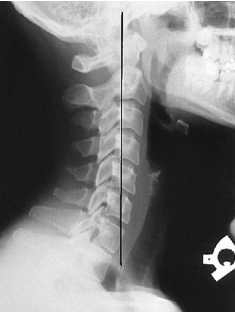

Q what is the name of this measurement? and what is the average + range?

A: Depth of Cervical Curve

from the superior posterior aspect of the odontoid to the posterior inferior corner of C7

assesses the depth of cervical lordosis. The average is 12 mm, with a range of 7-17 mm.